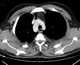

Right posterior aortic arch

Right-sided aortic arch is a rare anatomical variant in which the aortic arch is on the right side rather than on the left. During normal embryonic development, the aortic arch is formed by the left fourth aortic arch and the left dorsal aorta. [Source: Wikipedia ]